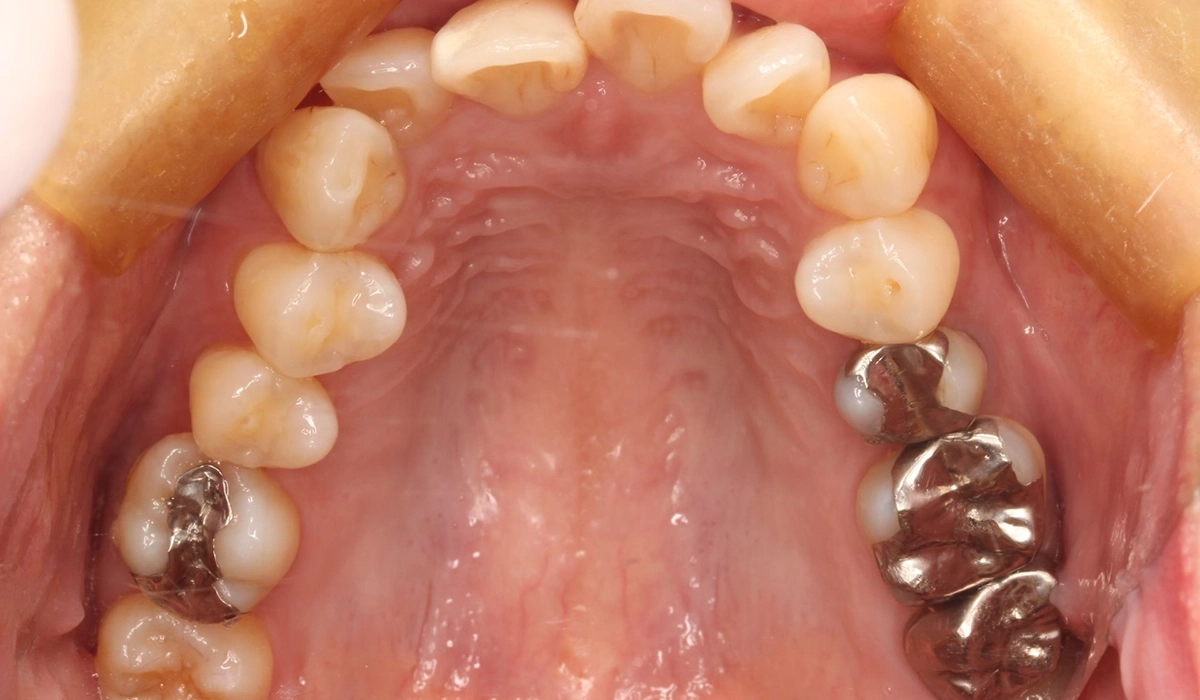

術前:上顎

術後:上顎